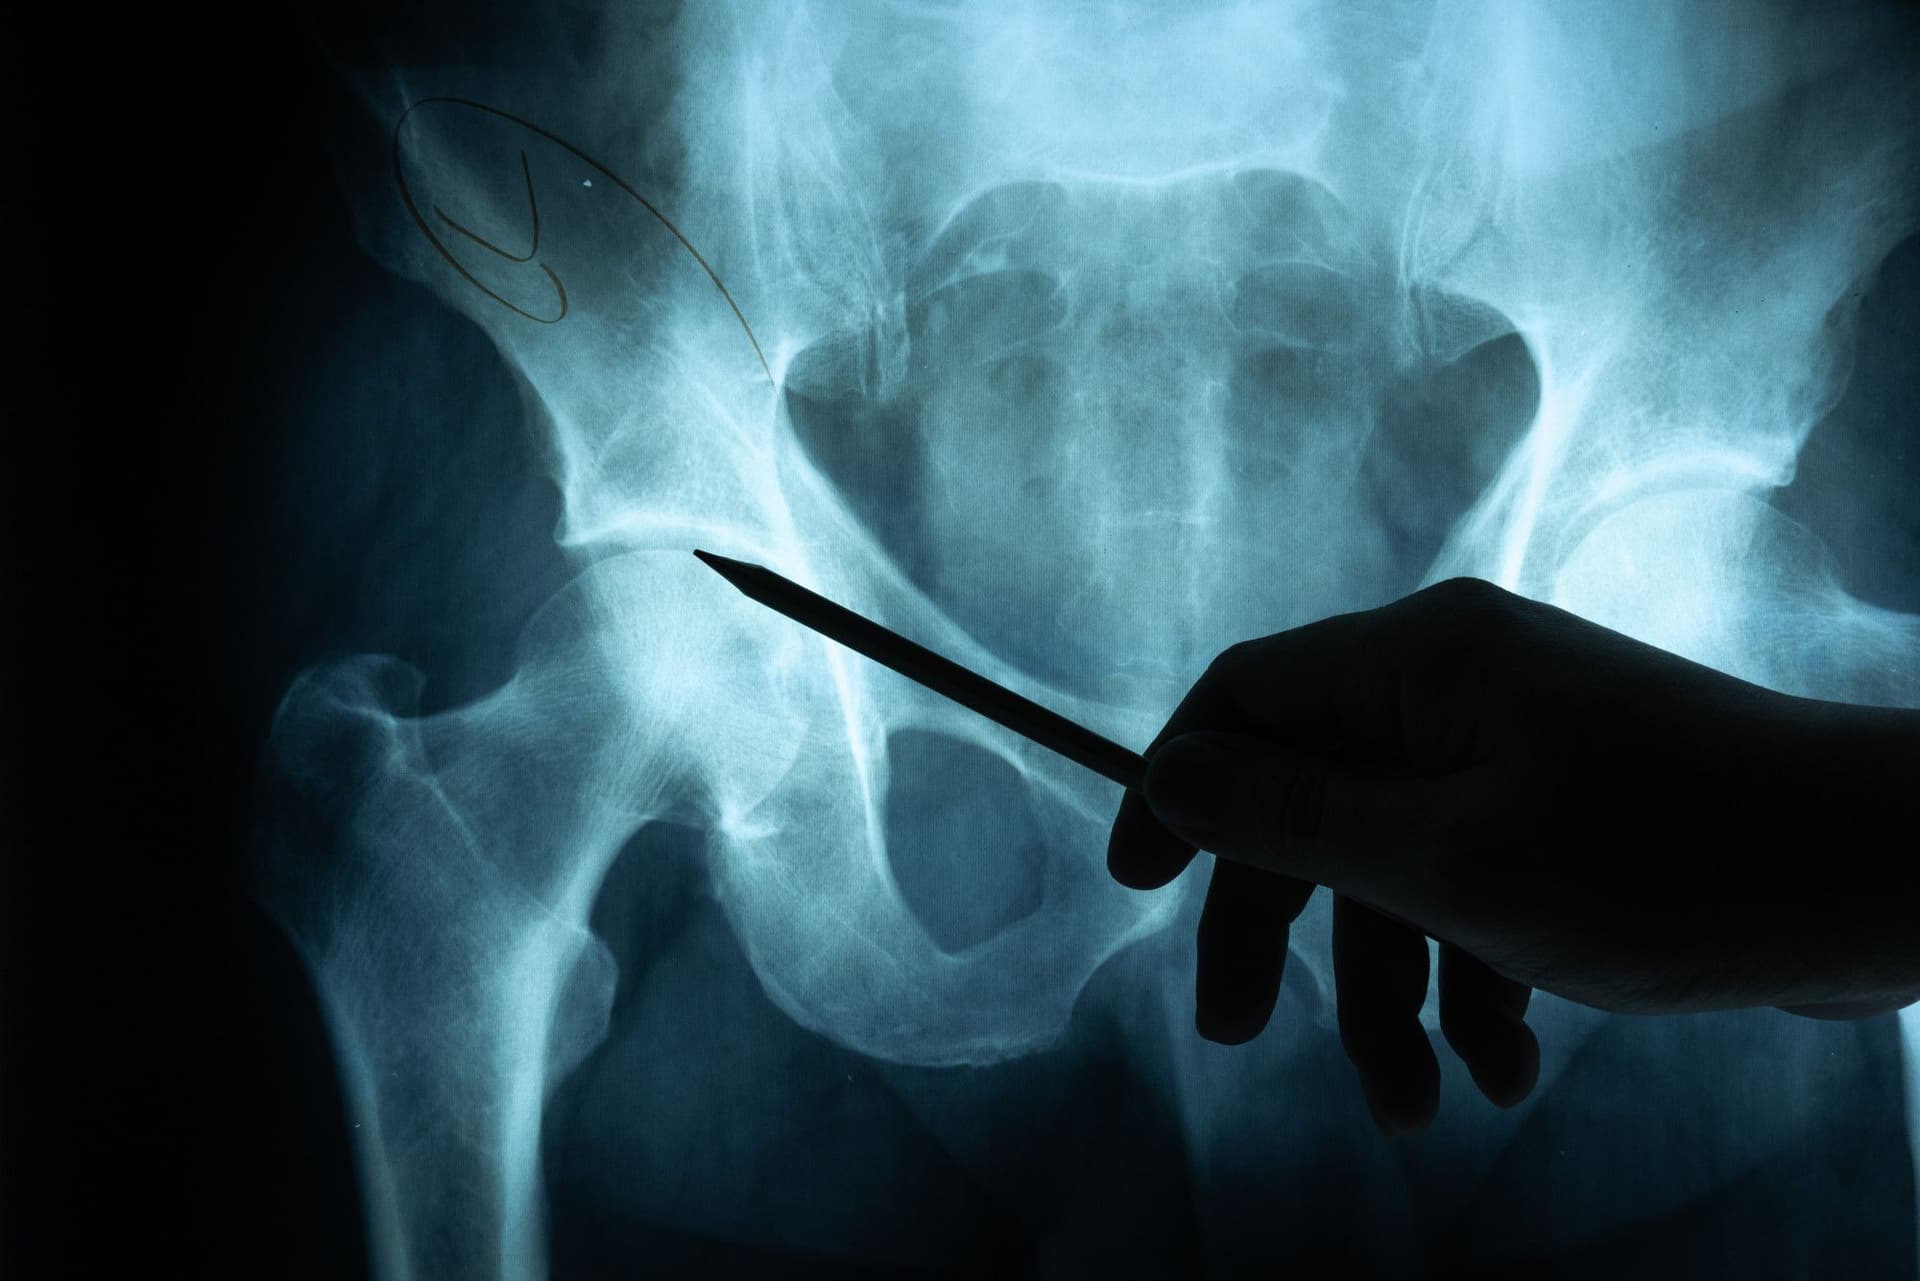

Anteroposterior pelvic radiograph should be obtained along with chest radiograph as an adjunct to the primary survey. During the primary survey, one assesses for major pelvic fracture including diastasis of the pubic symphysis, disruption of the sacroiliac joint, or vertical asymmetry of the hemipelvis segments.

Soft tissue shadowing or bladder displacement may suggest associated hematoma. After hemodynamic stabilization of the patient and completion of the primary surgery, additional radiographs including inlet and outlet views and CT scan of the pelvis may be obtained for better visualization and classification of identified injuries.